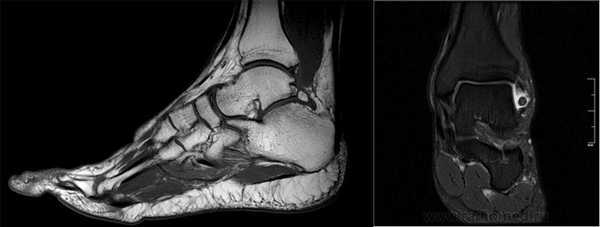

МРТ является ценным инструментом в комплексе диагностики ОХПТК для оценки отека костной ткани, а также выявления скрытых повреждений субхондральной кости и хрящевого покрытия, которые могут быть пропущены при стандартных рентгенограммах или даже КТ. МРТ - самый лучший инструмент оценки для определения стабильности и жизнеспособности фрагмента таранной кости при его отслоении и эта информация может быть решающей в тактике выбора того или иного метода хирургического лечения. Однако, для определения размеров отслоившегося фрагмента таранной кости наилучший метод КТ, так как данные размеров по МРТ могут не соответствовать действительности в сторону переоценки последних. Hepple с соавторами изучив многочисленные данные МРТ диагностики разработали систему классификации ОХПТК на основе этого метода (Табл. 2) [23]. Однако, наиболее широко принятая система классификации, основанная на КТ-это классификация Ferkel и Sgalione (Табл. 3; Рисунок 4) [24]. Классифицировать ОХПТК также возможно выполнить интраоперационно, на основе артроскопических данных о состоянии остеохондрального поражения. Наиболее широко используется система Ferkel/Cheng (Табл. 4) [25], эта система классификации, в отличие от обычных рентгенограмм, КТ и МРТ, лучше всего взаимосвязана с исходами лечения пациентов.

На КТ определяется остеохондральное повреждение таранной кости.

Однако порой на рентгенографическом снимке не видны некротизированные частицы кости из-за небольших размеров. В этом случае диагностику дополняют МРТ или КТ методиками. Оба метода позволяют поставить диагноз на ранних стадиях развития патологии.

На МРТ выявляется рассекающий остеохондрит с отделением костно-хрящевого фрагмента от таранной кости.